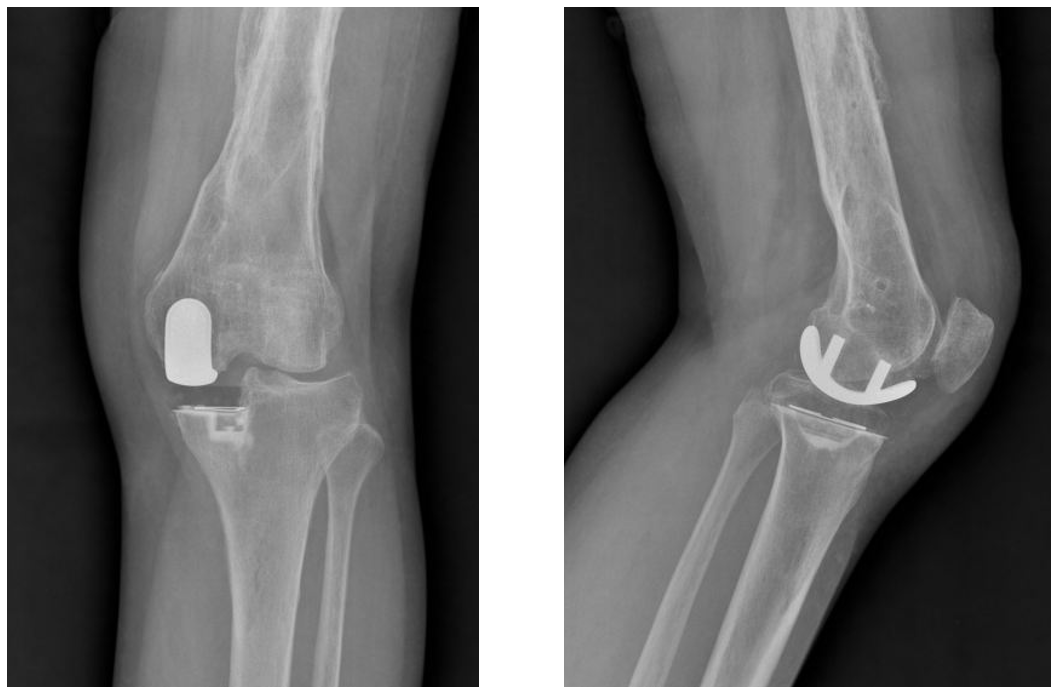

术后3个月复查情况

术后4年复查情况

术后6周、3月、6月 X-ray

术后半年